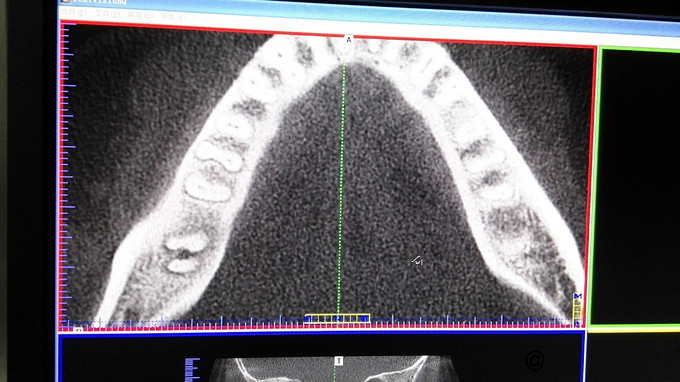

检查:右下7牙冠完整,近龈缘可见一突起脓包,少量脓血分泌物溢出,PD=10mm,余位点PD=3mm左右,叩痛(+),松动I度,电活力测试较正常牙迟钝。X线示:右下7牙槽骨水平吸收至根中,根分歧下低密度影像,远中根管增宽,可以根折。复拍CT:右下7根分歧下低密度影像,未达根尖,两根在舌侧融合,唇侧分开,唇侧无根柱,未见根折。

诊断:右下7牙周牙髓联合病变 治疗计划:右下7RCT+牙周基础治疗